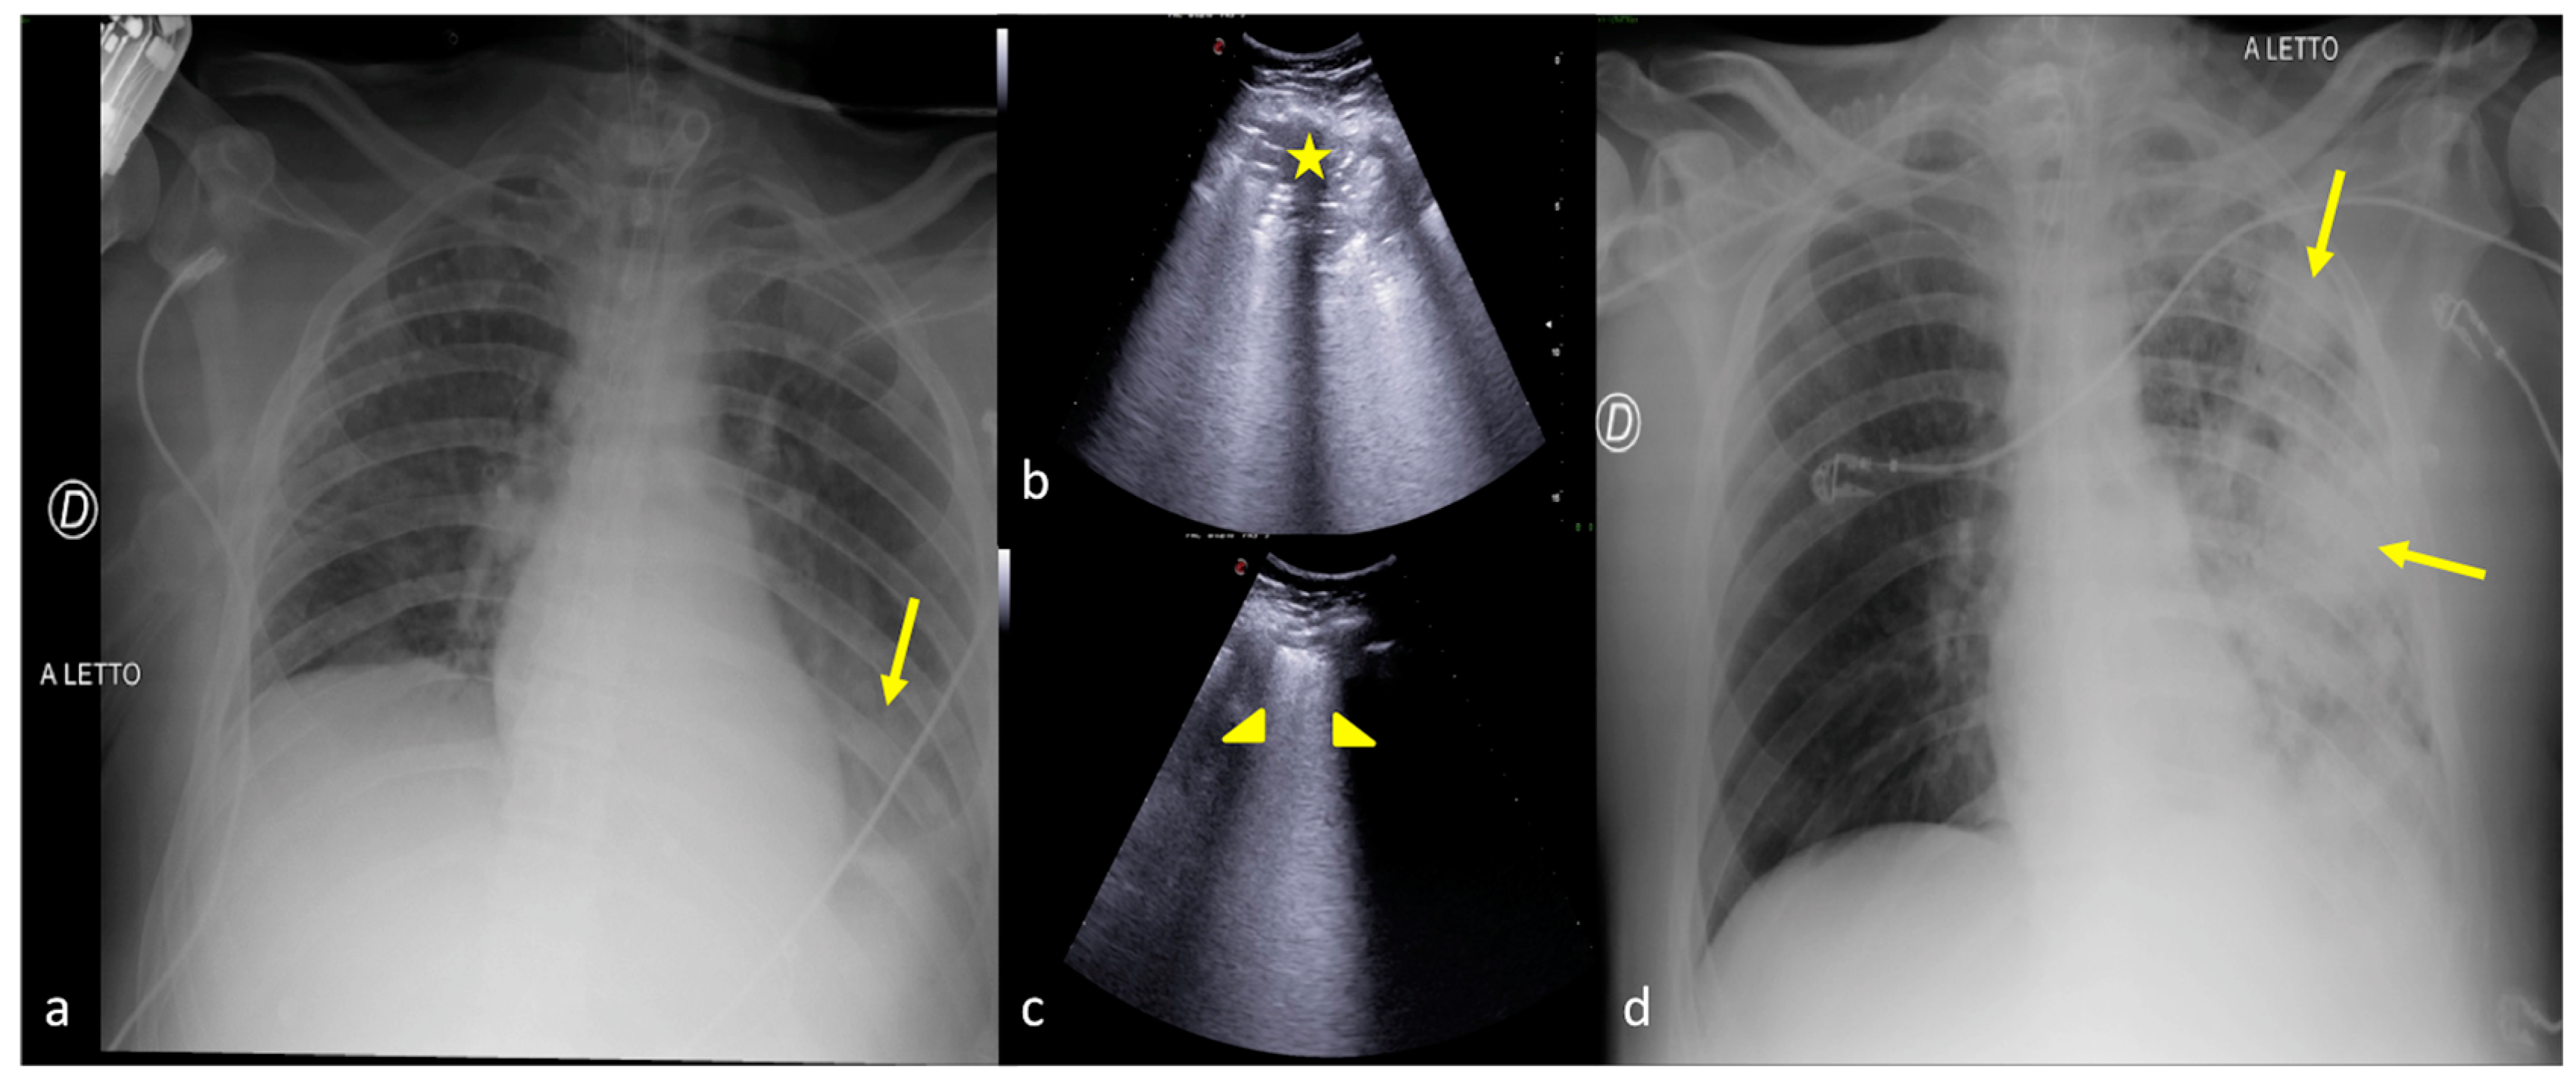

Figure 2.

Two examples of CXR and LUS diagnostic integration. Bedside CXR (a,d) and LUS diagnostic integration (b,c,e). In the first case (top line) the CXR showed small, blurred opacities in the left inferior pulmonary field (a, star); LUS of the left basis confirmed the consolidative area with hyperechogenic spots as signs of an air bronchogram (b, star). In the second case (below line), the CXR showed small, blurred opacities in the inferior pulmonary field bilaterally (d, arrowhead); LUS confirmed areas of lung consolidation with an air bronchogram in the lower right and left pulmonary fields without pleural effusion (c,e, arrowhead).